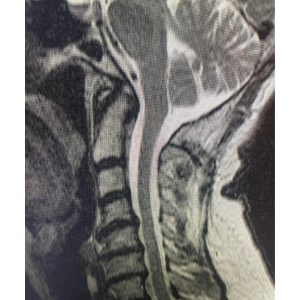

“A Chiari malformation results when a patient has too little room for their cerebellum in the back part of the skull. The cerebellar tonsils get forced down into the spinal canal. The result can be a syrinx or fluid filled cavity within the spinal cord that can cause pain, weakness and numbness. The Chiari malformation with or without a syrinx can also cause also headaches and other symptoms. Surgical treatment is most important when a syrinx is present to prevent progression of the neurologic symptoms.

These MRI scans show a patient before and after the Chiari decompression surgery that I performed. The surgery involves removing a portion of the back of the skull and the ring of C1 to relieve the pressure on the cerebellar tonsils and spinal cord. The bottom MRI was taken five years later and shows resolution of the syrinx. ”